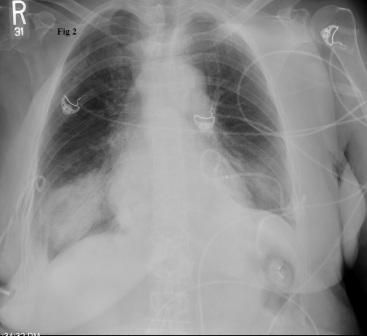

Figure 2.

A new chest radiograph showed diffuse infiltrates over bilateral lower lung fields, consistent with re-expansion pulmonary edema (REPE) (Figure 2). Noninvasive ventilation with biphasic positive airway pressure (BIPAP) was started. The patient’s symptoms improved gradually over the next 24 hours. Serial chest radiographs showed significant resolution of the previously seen bilateral infiltrates (Figure 3). However, over the following weeks, recurrent bilateral pleural effusions developed for which pleurodesis was done.